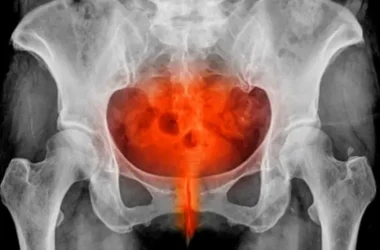

عظمة القص هي عظم مسطح وقوي يقع في منتصف الصدر، ويتصل بالأضلاع عن طريق الغضاريف. يشكل هذا الاتصال جزءًا مهمًا من القفص الصدري الذي يحمي الأعضاء الحيوية.

عندما يحدث تورم في منطقة عظمة القص، فهذا يعني وجود التهاب أو إصابة في العظم نفسه، أو في الغضاريف، أو الأنسجة المحيطة به. غالبًا ما يكون التورم مصحوبًا بألم وحساسية عند اللمس.